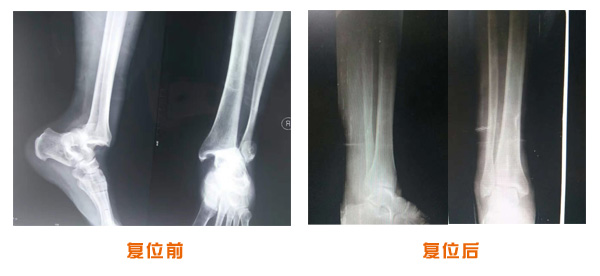

復位前后對比

肘關節脫位骨折治療前后對比